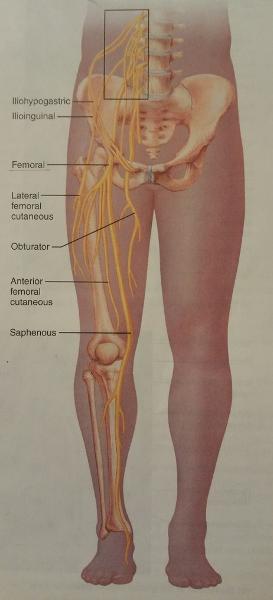

The nerves of the lumbar plexus serves which region and which body part?

Serves the lower abdominopelvic region and the anterior thigh

What is the largest nerve of the lumbar plexus?

Femoral nerve

The femoral nerve arises from the ventral rami of what lumbar nerves?

L2-L4

The femoral nerve innervates which group of muscles? (Give an example)

Anterior thigh muscles

Ex. Sartorius muscle

The cutaneous branch of the femoral nerve also serves what general feature of which general body part?

Supply the skin of the anteromedial surface of the entire lower limb

Identify the blanks.

Identify the blanks.

Identify the blanks.

Identify the blanks.

Identify the blanks.

Identify the blanks.

Identify the blanks.

Identify the blanks.

Identify the blanks.

Identify the blanks.